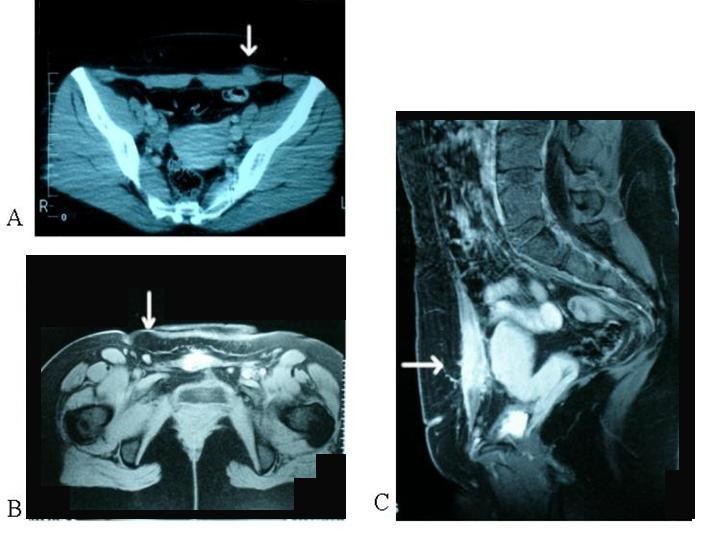

From www.ctisus.com

Scar Endometriosis Body MR Case Studies CTisus CT Scanning Scar Tissue Endometriosis Pain People with persistent, severe pain from endometriosis may need surgery to remove endometrial growths and scar tissue. Additionally, symptoms may vary based on the location and severity of. When endometrial tissue breaks down, it may irritate and inflame the surrounding area, causing scar tissue to grow. Not everyone with scar tissue or adhesions will experience symptoms. Endometriosis is described as. Scar Tissue Endometriosis Pain.

Scar Endometriosis Body MR Case Studies CTisus CT Scanning Scar Tissue Endometriosis Pain When endometrial tissue breaks down, it may irritate and inflame the surrounding area, causing scar tissue to grow. These nodules can appear in your. Endometriosis is described as the presence of functioning endometrial tissue outside the uterine cavity. Additionally, symptoms may vary based on the location and severity of. Not everyone with scar tissue or adhesions will experience symptoms. People. Scar Tissue Endometriosis Pain.